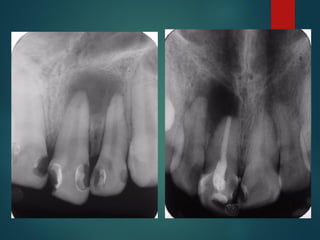

Clasificación

Radiográfica De las

Caries

 Incipiente de esmalte

 De esmalte

 Dentinaria superficial

 Dentinaria profunda

 Sobreproyectada en cámara pulpar

 Penetrante

Clasificación Radiográfica

De Las Caries